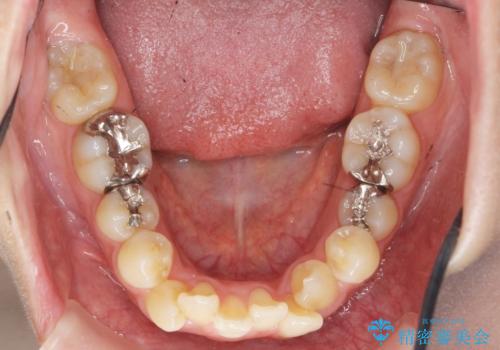

- 八重歯・がたつきのある歯並びの改善を求めて来院されました。

全部の歯が入り切るスペースがなかったため、小臼歯4本を抜去しワイヤーを用いたマルチブラケット矯正を選択しました。

歯並びの改善と共に、歯ブラシがしやすくなった!と喜んでいただくことができました。